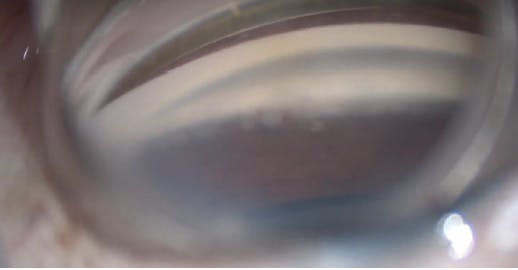

After IOL implantation and removal of the OVD from the capsular bag complex, 0.1 mL of carbachol intraocular solution 0.01% (Miostat, Alcon) was instilled in the anterior chamber to induce miosis. This was followed by an injection of OVD to inflate the anterior chamber and nasal angle. The operating microscope was tilted 45° toward the surgeon, and the patient’s head was rotated 30° away from the surgeon to aid in visualization of the nasal angle for the MIGS procedure. A left-handed Swan Jacob gonioprism was placed on the cornea with an OVD coupling agent. The TM was readily identifiable by its bright blue color from the trypan blue staining (Figure 8).

Figure 8. Intraoperative image of stained trabecular meshwork prior to Hydrus Microstent implantation.

I introduced the Hydrus Microstent injector into the anterior chamber through the temporal corneal wound. The injector cannula tip was engaged into Schlemm canal, and the Hydrus Microstent was deployed into the canal by scrolling the injector wheel forward. The injector lock was disengaged from the Hydrus Microstent, and the injector was removed from the anterior chamber. I used a Sinskey hook to adjust the positioning of the device and then removed the remaining OVD. At 6 months postoperative, the patient’s UCVA was 20/25 and IOP was 12 mm Hg on travoprost 0.04% and timolol maleate 0.5% daily.

Although it has long been documented that trypan blue aids in enhancing visualization for cataract surgery, recent advances in angle-based glaucoma surgery in adults have shown new uses for this vital dye, including staining of the TM and outlining of the collector channels.1-3 I personally had not seen a TM stain so brightly and vividly until this particular case. Most impressively, the staining persisted until the end of the procedure, despite having been applied before cataract extraction. The views seen in Figure 8 and Video 4 were captured after cataract extraction and IOL implantation.